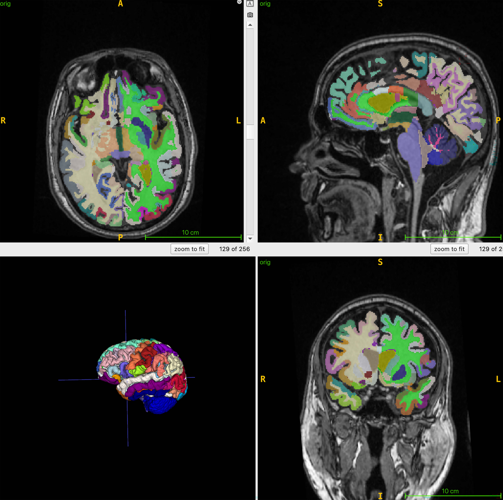

He explained that brain age is the computational estimation of chronological age from a structural MRI scan of the brain.

For the ongoing study, 1,164 healthy men and women, with an average age of 55.17, were examined with whole-body MRI.

The research team combined MRI imaging with T1-weighted sequences - a technique that produces images where fat appears bright and fluid appears dark.

Dr. Raji said that allows for optimal imaging of muscle, fat and brain tissue.

An (AI) algorithm was used to quantify total normalized muscle volume, visceral fat, subcutaneous fat - fat under the skin - and brain age.